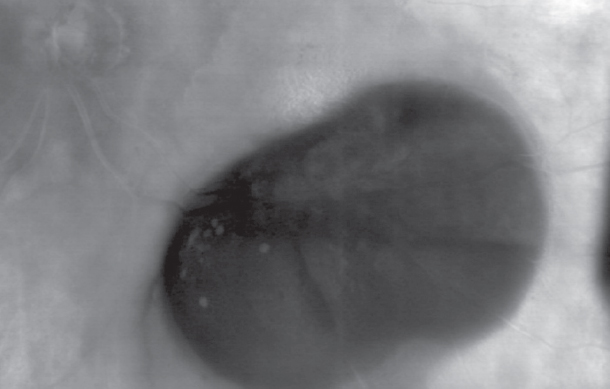

An ultrasound examination with a Doppler mapping in the lower part of the eyeball detected a rounded lesion of a heterogeneous echo density, which was 0.32 × 0.80 cm in the size and had no vascular signal in the center of the lesion (Fig. 2).

Fig. 2. Ultrasound procedure: a – B-scan mode; b – Doppler mapping mode / Рис. 2. Ультразвуковое исследование: а — режим В-сканирования; b — режим доплеровского картирования

OCT revealed a high elevation of the retinal pigment epithelium, and although its content could not be confidently differentiated, in combination with the presence of a subretinal blood, its hemorrhagic nature could be assumed. This was also confirmed by the ultrasound data which demonstrated a hypointense signal in the neoplasm center.